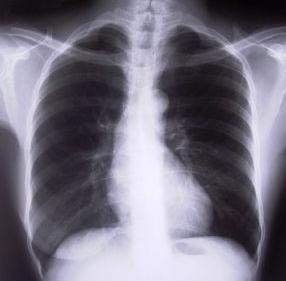

La pleuresia es una inflamación de la pleura, es decir, de la membrana serosa que recubre los pulmones y se repliega sobre todos los órganos contenidos en el tórax y entre sus lóbulos.Se trata de una inflamación que puede ser causada por traumatismos en el tórax, alteraciones costillares o debido a la propagación de inflamaciones en el pulmón, sobre todo a quienes sufren de reumatismo.La pleurasia casi siempre va precedida de escalofríos y fiebre moderada con más de 120 pulsaciones por minuto. El enfermo refiere dolor del costado en el lugar inflamado, dolor que aumenta con los movimientos de la respiración; la cual acostumbra a ser superficial, breve y jadeante. Además encontramos tos y estornudos, orina escasa y oscura y puede haber estreñimiento.La pleurasia más dolorosa y que más impide y dificulte la respiración es la situada sobre el diafragma.